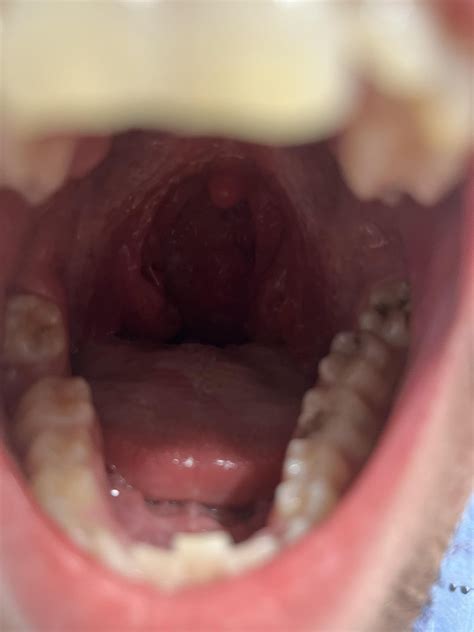

Understanding the Tonsillar Lymph Node

The tonsillar lymph node, often referred to as the jugulodigastric node, is situated just below the angle of the jaw, near where the tonsils are located. Because they are positioned so close to the throat and mouth—areas frequently exposed to environmental pathogens—they are often the first line of defense to become active when an infection occurs.

When you visit a healthcare provider, they will typically begin with a physical examination to check the size, texture, and tenderness of the node. They will also look for other signs of infection in the throat and mouth.